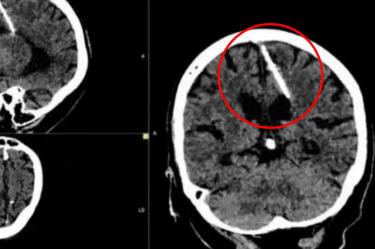

Lo que era un chequeo médico rutinario se convirtió en una pesadilla luego de que especialistas hallaron una aguja de 3 centímetros de largo en el cerebro de una mujer de 80 años en Rusia.

Aunque no se han revelado detalles del lugar exacto en donde ocurrió este suceso, o la fecha en la que se registró, autoridades sanitarias dijeron que la aguja se encontraba en el lóbulo parietal izquierdo de la mujer anónima quien al parecer la tuvo alojada en el cerebro desde que era una bebé y nunca le provocó molestias ni dolores de cabeza.

Los médicos decidieron no retirar el objeto del cebero de la mujer, ya que no representa un peligro para ella y ha vivido sin problemas de salud durante toda su vida, por lo que someterla a una cirugía podría ser riesgoso por su edad y podría ser grave para ella.